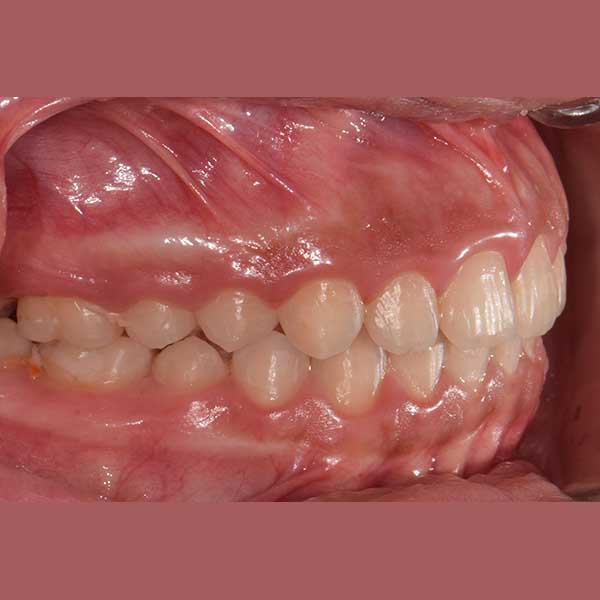

AFTER

راجعتني هذه الآنسة الصغيرة برفقة والدتها، وكانت الشكوى الرئيسية هي بروز الأسنان بشكل كبير، مما أثر سلباً على نفسيتها وثقتها بابتسامتها، بالإضافة إلى تأثيره على نطق بعض الحروف.

بعد الفحص الدقيق، وجد الدكتور خالد الكاتب أن الأسنان العلوية متقدمة على السفلية بمسافة كبيرة (8 مم)، وأن السبب الجذري للمشكلة هو تراجع الفك السفلي. ونظراً لصغر عمر المراجعة ورفض الأهل لخيار قلع الأسنان، تم وضع خطة علاج ذكية تعتمد على تقديم الفك السفلي للأمام باستخدام جهاز وظيفي ثابت، وهو خيار مثالي في مرحلة النمو.

كما تظهر الصور، تم تصحيح مشكلة البروز بالكامل. تقدم الفك السفلي إلى وضعه الصحيح، مما أدى إلى تناسق رائع في ملامح الوجه وإطباق مثالي للأسنان. الأهم من ذلك، استعادت صديقتنا الصغيرة ابتسامتها المشرقة وثقتها بنفسها.